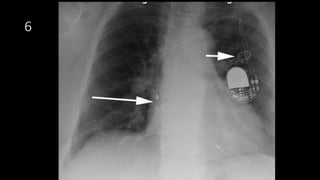

A 61-year-old man presented with worsening right thoracic pain and dyspnea three days after being discharged from cardiology following pacemaker implantation for sick sinus syndrome. A 60-year-old woman with an implanted pacemaker presented with dizziness and fainting. A 77-year-old woman who had a pacemaker implanted for symptomatic sinus bradycardia presented one week later with continuous chest pain. An elderly patient presented 6 months after pacemaker implantation with a recurrence of exertional shortness of breath.